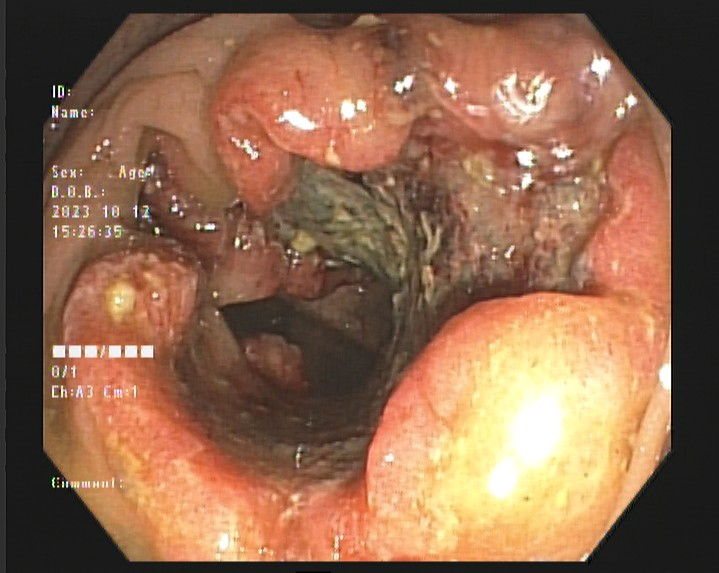

结肠癌进展期